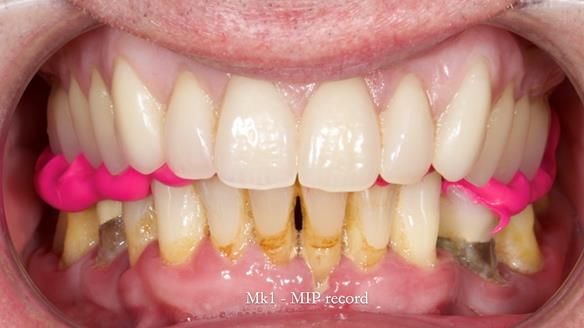

Jeremy’s upper bridge, supported by the canine teeth (13 and 23), was failing both aesthetically and functionally.

- On smiling, the bridge was clearly visible and did not look natural, as the ceramic had been ground back.

- Functionally, the bridge was unstable, due to Periodontitis – Stage IV, Grade C (generalised).

- Retain the upper canines (13 and 23) after root canal treatment, to support a Mk1 immediate complete denture.